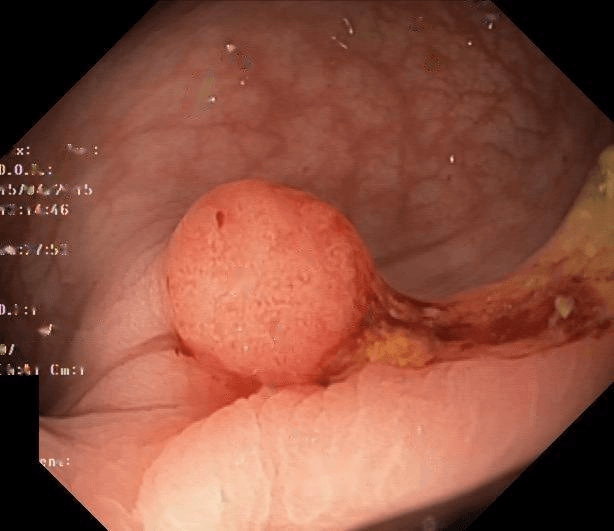

Refer to caption

(a) No abnormality

(b) Polyp

(c) Oesophagitis

(d) Ulcerative Colitis

Figure 1: Illustrations of question-answer pairs along with common abnormalities in gastrointestinal image from ImageCLEFmed-MEDVQA-GI-2023 dataset

The new dataset released for the ImageCLEFmed-MEDVQA-GI-2023 challenge is based on the HyperKvasir dataset [29], the largest gastrointestinal collections with more than 100,000 images, with the additional question-and-answer ground truth developed by medical collaborators. The development set and test set include a total of 3949 images from different procedures such as gastroscopy and colonoscopy, spanning the entire gastrointestinal tract, from mouth to anus. Each image has a total of 18 questions about abnormalities, surgical instruments, normal findings and other artefacts, with multiple answers possible for each, as shown in Table 1. Not all questions will be relevant to the provided image, and the VQA system should be able to handle cases where there is no correct answer. Figure 1 depicts several examples of question-answer pairs on common abnormalities in gastrointestinal tract, such as Colon Polyps, Oesophagitis, and Ulcerative Colitis. As shown in Figure 1(d), there are three possible answers to the question "What color is the abnormality?": "Pink," "Red," and "White", and a typical VQA system should be able to identify all three colors. In general, the image may contains a variety of noise and components that locates across abnormalities, such as highlight spots or instruments, which pose a significant challenge in developing efficient VQA systems for gastrointestinal domain.